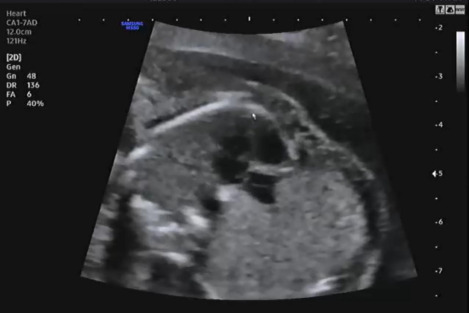

침대에 누워 복부초음파를 보는데 먼저 자궁경부 길이 등을 확인하고 양수량이 적당히 있는지 확인을 했다. 다행히 나는 자궁경부 길이가 4.22cm고 양수량도 적당히 있어서 조산위험이 없다고 했다. 자궁경부 길이가 짧을수록 조산위험이 크기 때문에 절대 안정이 필요하다.